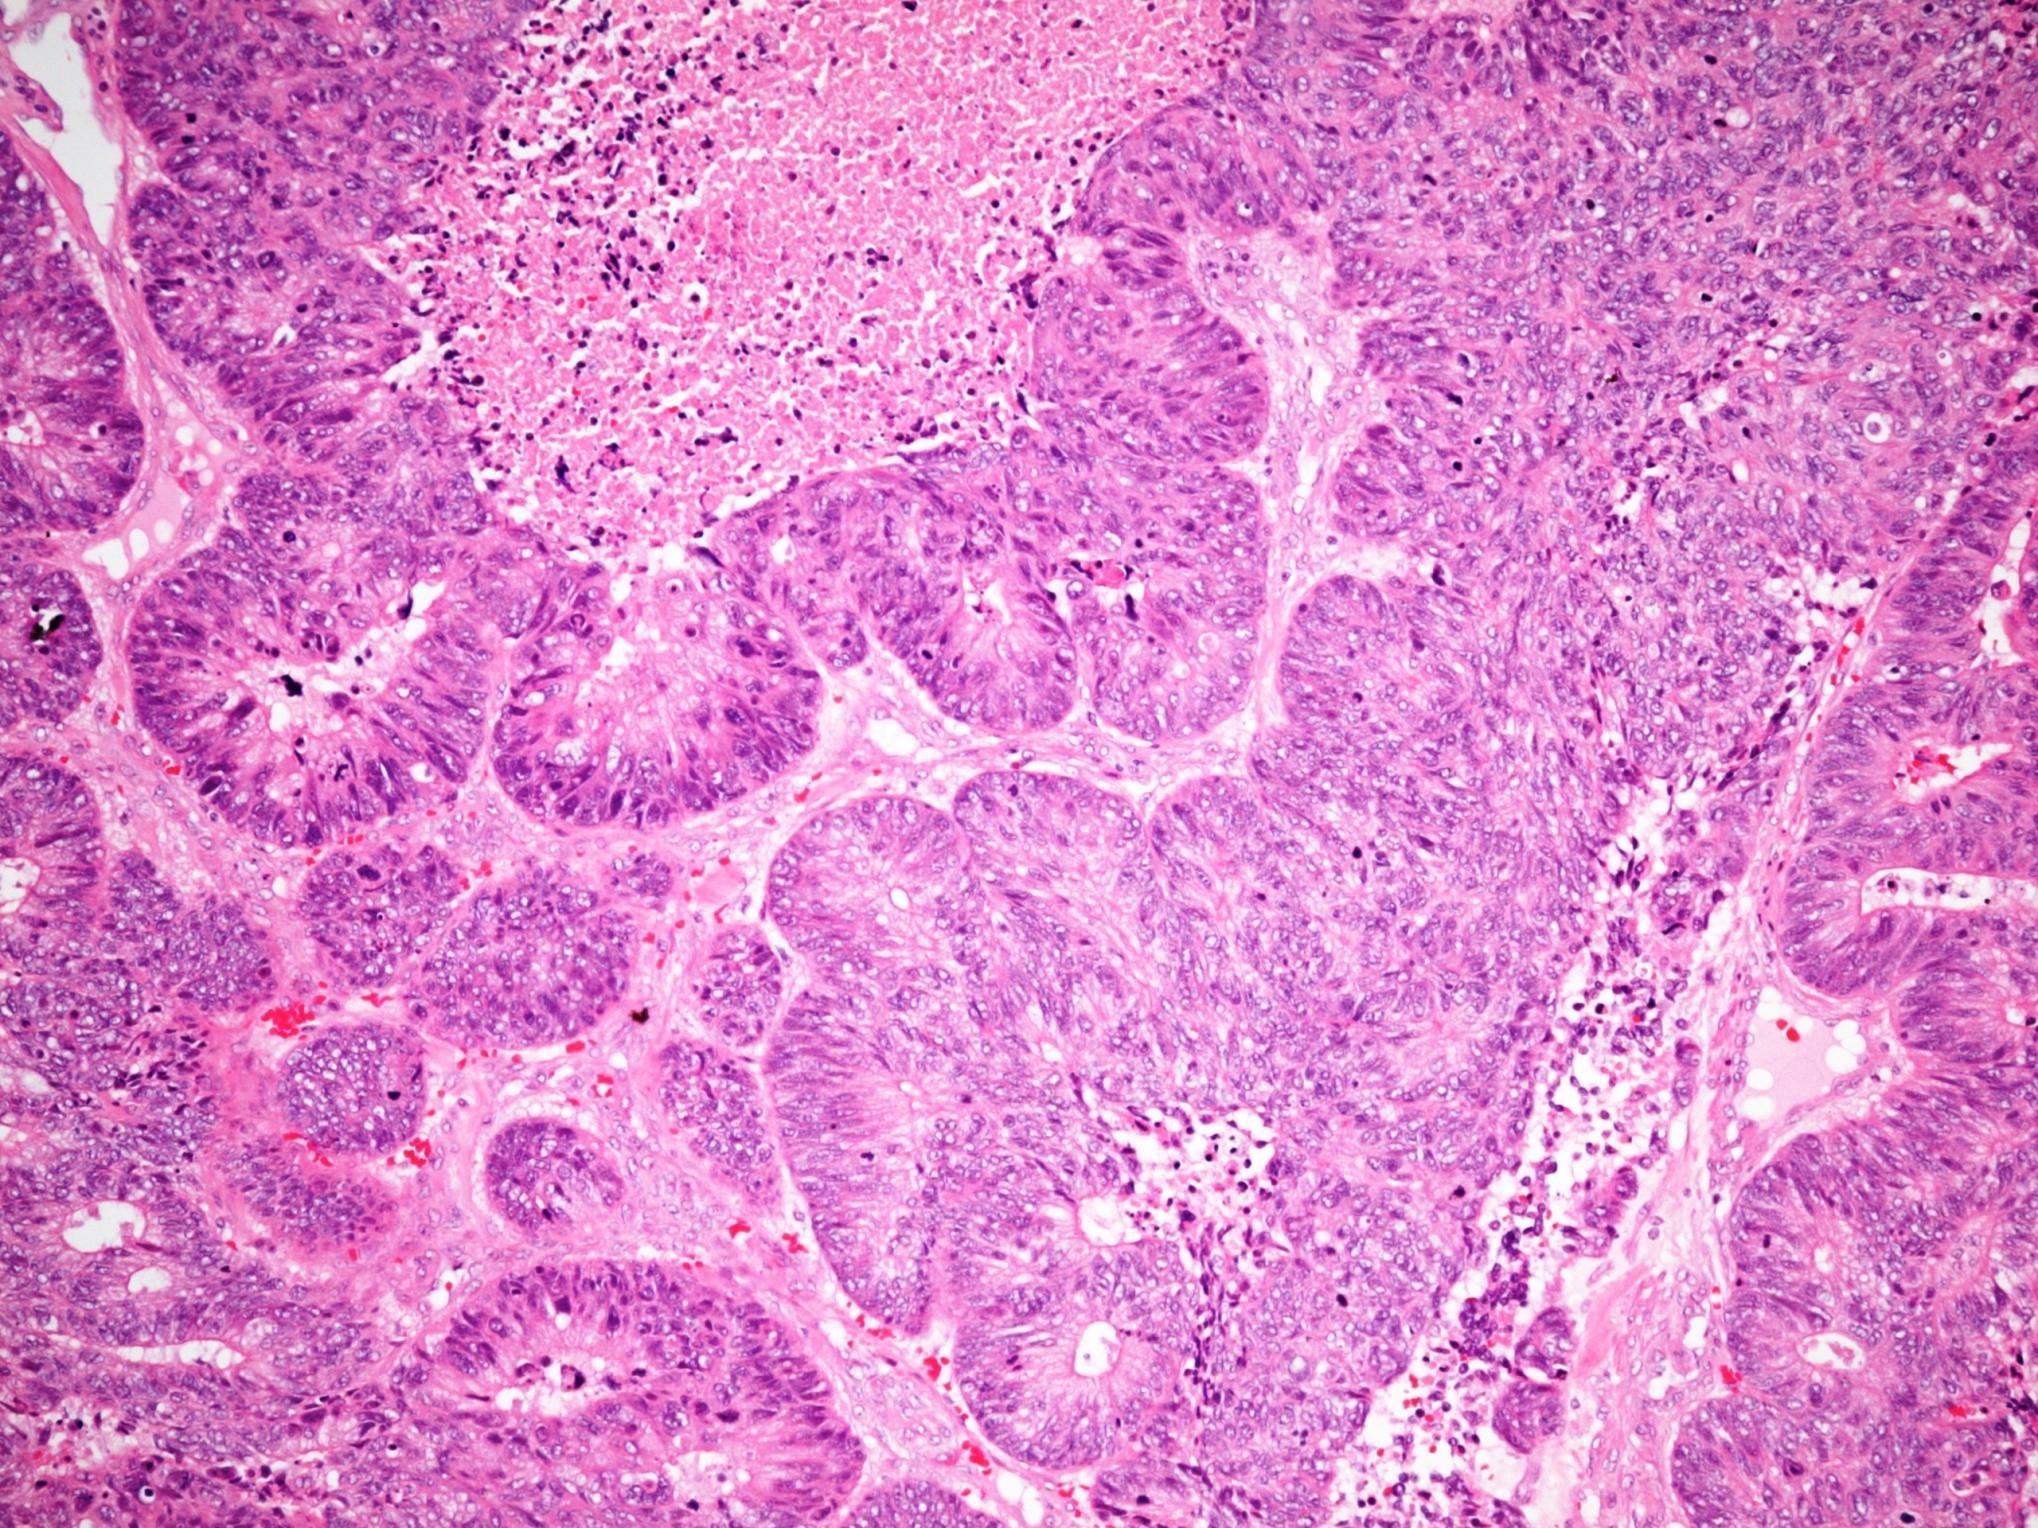

Mucoepidermoid carcinoma

 Wide age range and most common malignant salivary gland tumour in

adolescents and children

 3 types of cells

Epidermoid cells

Mucous cells

Intermediate cells

Clear cells

Grading

Cystic change

Necrosis

Neural invasion

Anaplasia

>4 mitoses / 10 hpf

 Low grade can be well circumscribed

 Often a nesting pattern

 Sometimes lymphoid stroma